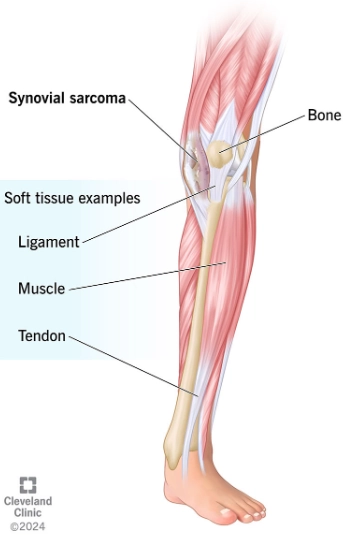

Sarcoma bao hoạt dịch (Synovial sarcoma)